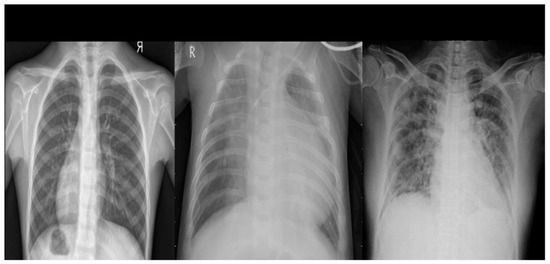

It was developed by a team of researchers from Qatar University, Doha, Qatar and Dhaka University, Bangladesh, in collaboration with physicians. It includes chest X-ray images of patients with COVID-19, as well as normal images, viral pneumonia images and lung opacity images. The database includes a total of 3616 positive cases of COVID-19, 10,192 normal images, 6012 cases of pulmonary opacity and 1345 cases of viral pneumonia (show Figure 2).

Figure 2. Example of chest X-ray images from the COVID-19 Radiography Dataset.

Algorithms 18 00210 g002